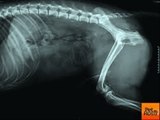

Dog diagnosed with skin cancer has bucket list to complete!